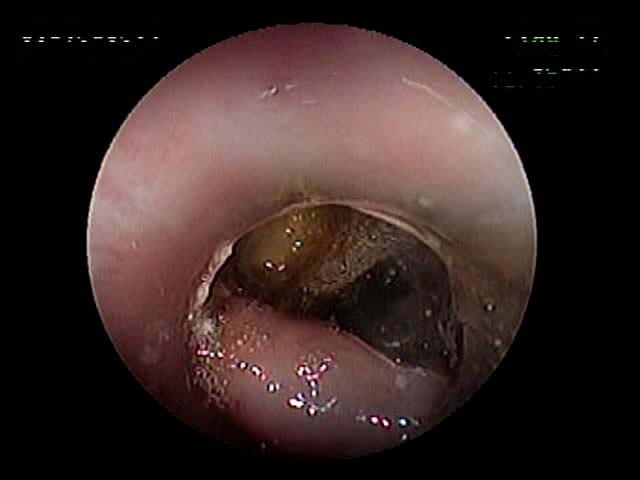

お正月に庭石を食べたというご連絡 がありました(10kgのワンちゃん)。数日経っても便に出てこなく、嘔吐があったとのことでした。X線を撮ってもまだ胃内にあるのが確認されたため、内視鏡を実施しました。胃内の十二指腸につながる通路にはまっていました(写真)。ワイヤーで引いても引き出すことが困難だったため、このあと手術にて摘出しました。

どの件も内視鏡で工夫して摘出に全力を尽くしますが、どうしても限界があります。その見極めは、経験予測ですがやはり実施してみないとわかりませ ん。今回も内視鏡実施後、摘出困難と早い段階で判断して試験開腹に切り替えました。麻酔時間の件があるからです。それにしても、トータル2時間以内に終えることができました。

3日間で退院しましたが、飼い主様はその間にすでに庭石(玉砂利)をコンクリートで固めていただけました。同じことは起こさせない、飼い主様の早い対応に感謝いたします。

幽門洞にはまっている庭石を

ワイヤーでとらえようとする様子